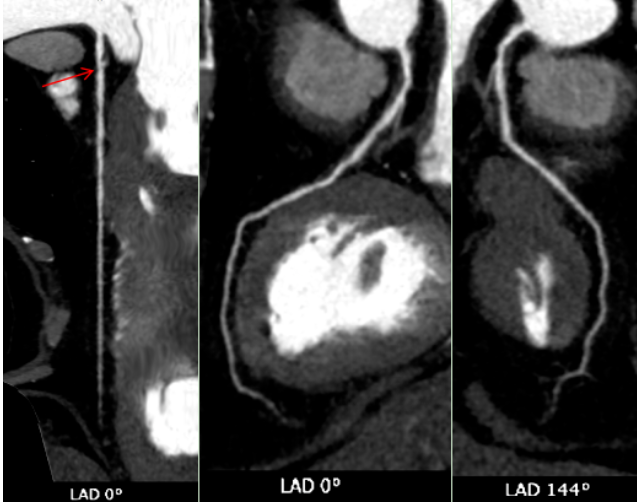

随即,张老先生被安排进行了一项关键检查:冠状动脉CT血管成像(CCTA)。对于一位81岁高龄、心律不齐且难以长时间屏气的老人来说,传统的CT扫描可能因呼吸运动和心跳产生伪影,导致图像模糊、诊断困难。然而,这次检查使用了——GE 256排宽体探测器CT。其核心优势在于“快”与“宽”:探测器覆盖范围宽,仅需0.3秒的极短扫描时间,就能完成心脏区域的完整数据采集。这意味着患者可以自由呼吸,无需刻意屏气,并且高速扫描能“冻结”心跳,极大削弱了心律不齐对图像质量的干扰,从而获得清晰、可靠的心脏血管图像。

CT表现:冠状动脉粥样硬化,左冠状动脉前降支近端中度狭窄,左冠状动脉前降支心肌桥形成。

正常情况下,血管走在心脏表面,收缩舒张自由;而当血管被心肌“桥”覆盖时,心脏每次收缩挤压,都可能短暂压迫这段血管,影响远端的血液供应。狭窄加上心肌桥的叠加效应,很好地解释了他为何出现胸闷、胸痛(心绞痛)和心律不齐的症状——心肌正在发出“缺血”的求救信号。

冠状动脉CTA已成为筛查和诊断冠状动脉疾病的无创性“金标准”之一。它通过静脉注射对比剂,利用CT快速多层扫描和三维重建技术,直观展示冠状动脉的走行、管腔狭窄程度、斑块性质(如钙化斑块或软斑块)以及血管壁的情况。对于像张老先生这样的病例,CTA不仅能精准测量狭窄百分比,还能识别心肌桥这一解剖变异,评估其与狭窄的相互影响,为临床制定治疗方案(是药物保守治疗,还是需要介入支架或外科搭桥)提供了至关重要的参考。报告中提到的宽体探测器技术,代表了当前CT发展的前沿方向,特别适用于心率快、心律不齐、不能配合屏气或身体虚弱的患者,极大地拓宽了心脏CT检查的适用人群和诊断成功率。